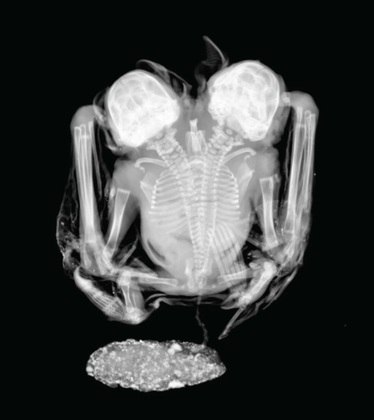

X-rays show that bats have separate heads and hearts, but a convergent spine (Credit: Laboratório de Radiografias, Museu Nacional, Universidade Federal do Rio de Janeiro)

Male bats have separate heads and necks, but their spines eventually merge into one, according to an x-ray.

They also have two separate but similar sized hearts.